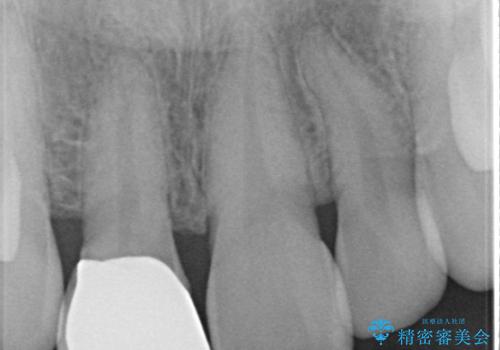

- 患者様は、前歯の被せ物の形や色が不自然で気になるというお悩みを抱えて来院されました。

診察の結果、既存の被せ物は古い素材で作られており、周囲の歯との調和が難しいことが分かりました。患者様とカウンセリングを重ね、アライナー矯正で歯列のガタツキを修正後、。より自然で審美的な仕上がりを目指してオールセラミッククラウンでの治療を提案しました。